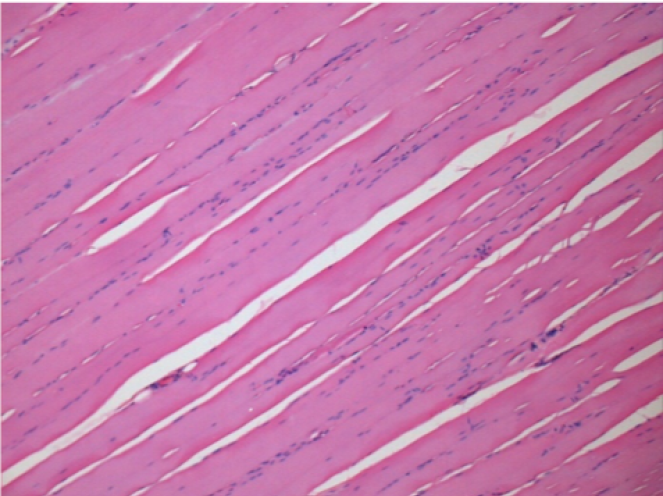

بعد 10 أيام من حقن إندوبيل

10 أيام بعد حقن إندوبيل 0.1 مل في العضلة أمام الظنبوب الأيمن.

هنا قد ترى تشكيل الفجوات التي تحيط بها الخلايا اللمفاوية. الفجوات تختلف عن نخر الأنسجة. يرتبط وجود الخلايا اللمفاوية بنفاذية أغشية الخلايا.

L : Control-100xD10

R:100xD10

R :200xD10

R :400xD10